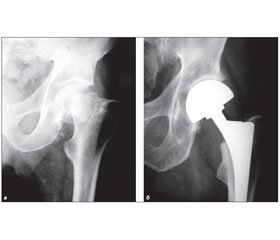

Хирургическое лечение медиальных переломов шейки бедренной кости

Работа базируется на результатах оперативного лечения 174 пациентов с медиальными переломами бедренной кости. Медиальные переломы относятся к тяжелым повреждениям проксимального отдела бедренной кости. Это связано с высокой вероятностью развития осложнений. Целью нашего исследования является анализ результатов лечения у больных с медиальными переломами и определение оптимального метода лечения этих переломов.

Ендопротезування тазостегнового суглобу є тяжкою і високотехнологічною операцією. Топографо-анатомічні властивості ділянки операції специфічні в кожному окремому випадку, тут проходять великі судинно-нервові утворення [4–6]. Ця методика дозволяє: відновити опорнiсть кінцівки, активізувати хворого в ранньому післяопераційному періоді, створити умови для самообслуговування.